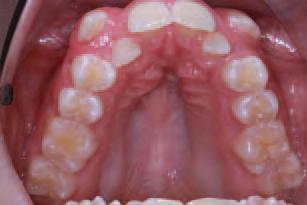

Issuu converts static files into: digital portfolios, online yearbooks, online catalogs, digital photo albums and more. Sign up and create your flipbook.